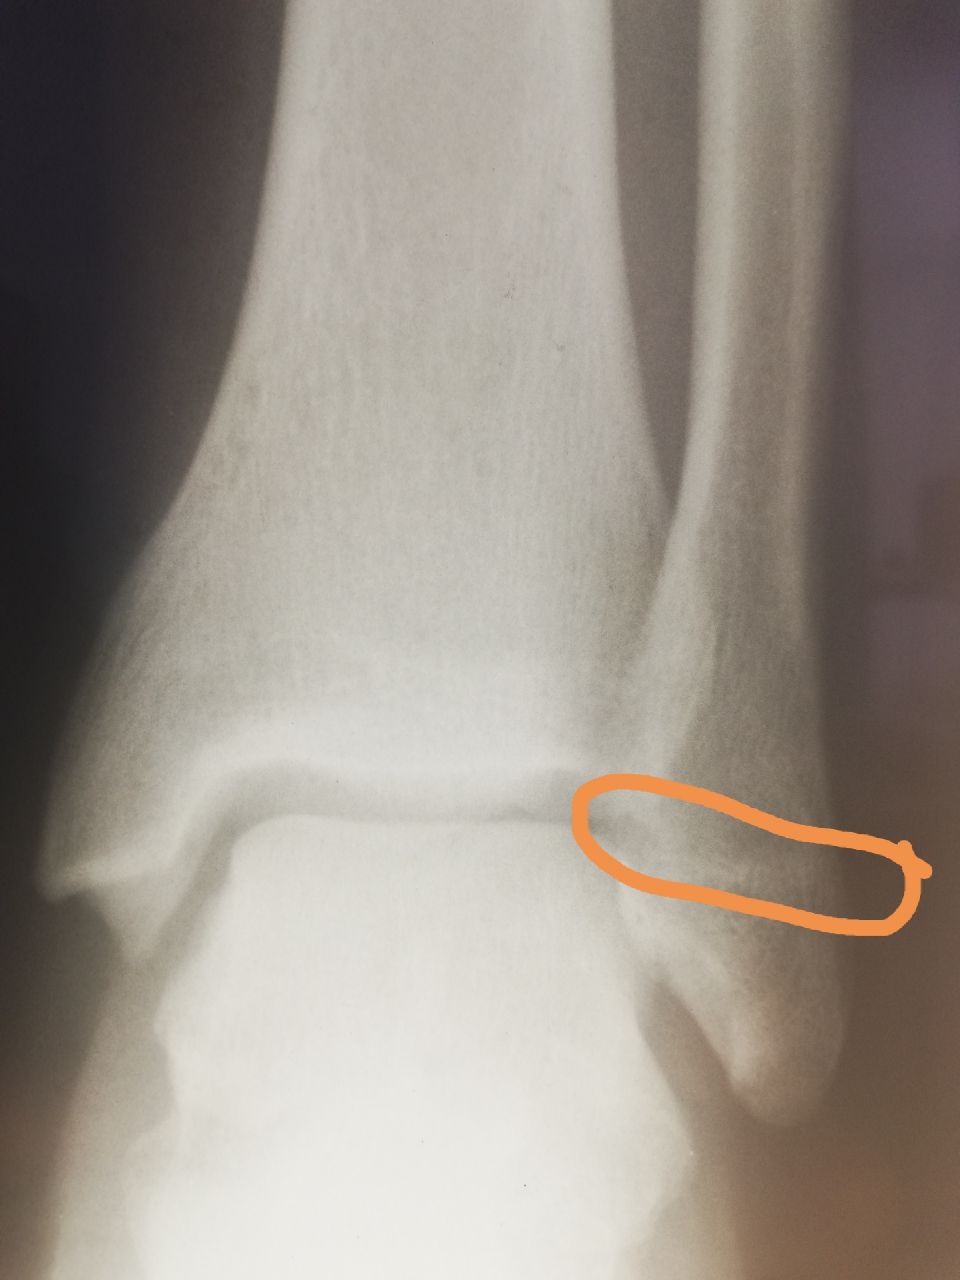

Здравствуйте! Мужчина, 37 лет, 3-4 недели назад была травма. Смущает отмеченный участок на латеральной лодыжке. Как думаете, есть ли перелом? И если есть, можно ли сказать о его консолидации?